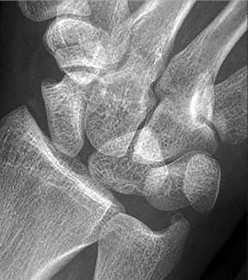

Question 8:

A 22-year-old male sustains a proximal pole scaphoid fracture. Which of the following best describes the predominant arterial supply to the scaphoid that makes this specific fracture pattern highly prone to avascular necrosis (AVN) and nonunion?

Correct Answer: Dorsal carpal branch of the radial artery entering distally and flowing retrograde

Explanation:

The scaphoid is primarily supplied by the dorsal carpal branch of the radial artery (supplying 70-80% of the bone, including the proximal pole). These vessels enter the scaphoid distally at the dorsal ridge and flow in a retrograde fashion toward the proximal pole. Because of this retrograde blood supply, fractures at the proximal pole disrupt the vascularity to the proximal fragment, leading to high rates of AVN and nonunion.